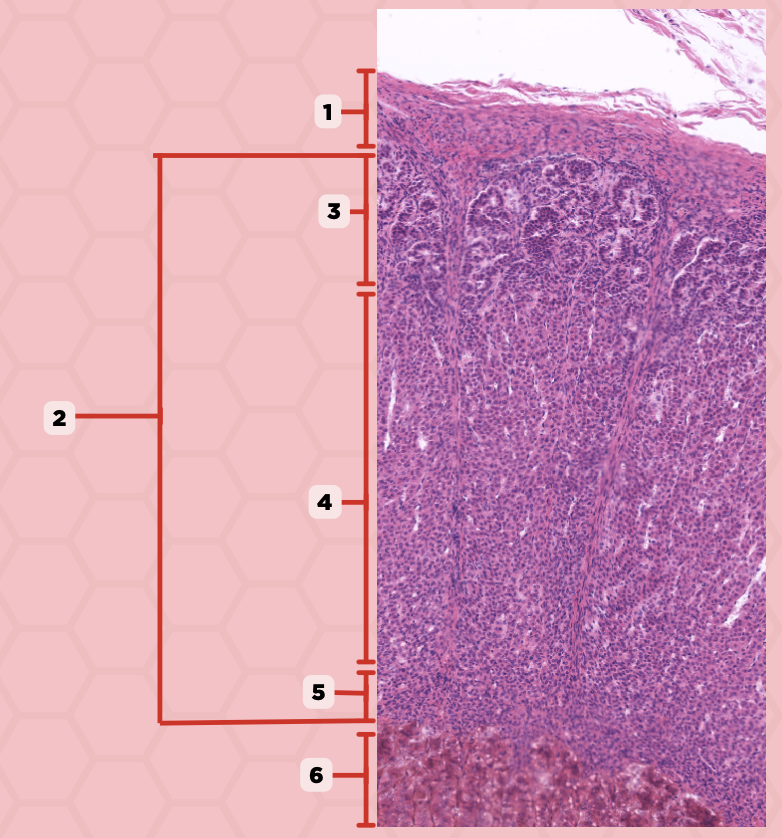

Adenohypophysis

What does #1, #4, and #5 form?

Pituitary

Identify the specimen.

Intermediate Lobe

Identify the structure labeled as 1.

Posterior Lobe

Identify the structure labeled as 2.

Pituitary Stalk

Identify the structure labeled as 3.

Pars Tuberalis

Identify the structure labeled as 4.

Anterior Lobe

Identify the structure labeled as 5.

Neural Ectoderm

What ectoderm is #2  derived from?

Oral Ectoderm

What ectoderm #1, #3, & #4 derived from?